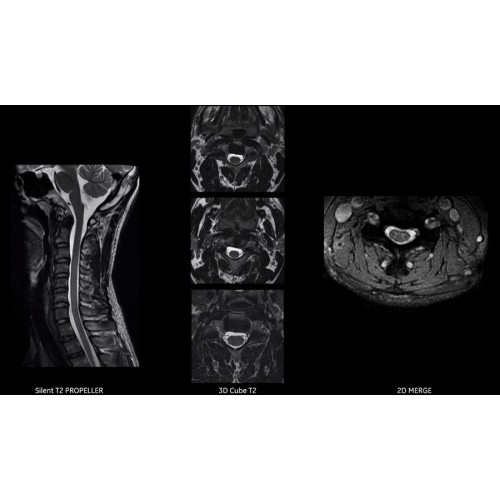

• Технология Digital Surround Technology (DST) — это новая технология объемной оцифровки данных, объединяющая сигналы от каждого элемента катушки. Прекрасное соотношение сигнал/шум и чувствительность поверхностных катушек в сочетании с превосходной однородностью и высокой проникающей способностью встроенной радиочастотной катушки — все это позволяет создавать качественные изображения не только позвоночника, но и всего тела.

Благодаря революционному программному пакету Silent Suite уровень шума снижается до 77 дБ, что всего на 3 дБ выше уровня окружающей среды. Программный пакет Silent Suite теперь включает полный пакет приложений для исследования ЦНС (T1, T2 FLAIR, DWI10, МРА). Кроме того, мы расширили возможности визуализации Silent за пределы ЦНС для исследований скелетно-мышечной системы и позвоночника. Silent Suite – платформа, содержащая в себе все импульсные последовательности для бесшумного сканирования.